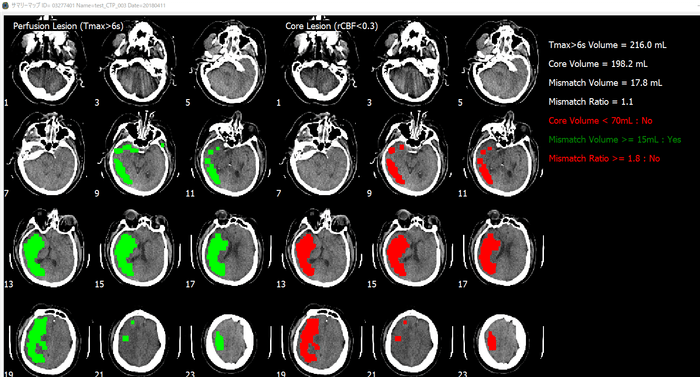

脳画像解析プログラム PMAneo(以下 PMAneo)は、MRI拡散強調画像から低ADC値領域を計測、またMRIまたはCT灌流画像からCBF、CBV、最大遅延時間を計測し、脳血流低下領域の容積およびこれらの差と比を算出、表示する、全自動脳画像解析ソフトウェアです。

PMAneoは、虚血コアと低灌流領域に相当する体積及びミスマッチの自動解析を数分で行う脳画像解析プログラムです。

急性期脳梗塞に対する血管内血栓回収療法の適応患者の選択の支援やワークフロー改善に向けて、使用されることを想定しています。